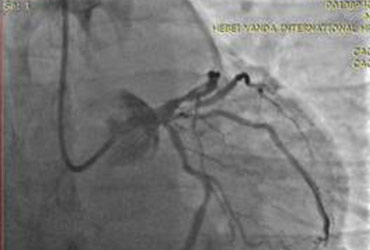

患者的成功抢救,充分体现出燕达医院开展学科建设及多学科会诊机制的实施成效。当然,对于由急诊科、心内二科、重症医学科(ICU)、检验科、影像科等多学科所组成的这支“快速反应部队”来说,(zui)黄金的回忆莫过于帮助一个又一个原本飘摇可危的生命回归到它原有的健康轨